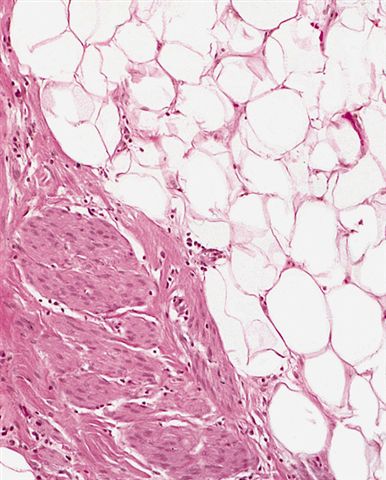

Microscopic (histologic) images

Contributed by Michael Clay, M.D., Melanie Bourgeau, M.D. and AFIP

Metaplastic change:

- Lipoleiomyosarcoma

- Liposarcoma with leiomyosarcomatous differentiation

- Both components are low grade

- Variable amount of the smooth muscle component, which can be seen in association with large vascular walls

- Similar biology and can dedifferentiate

- ALT / WDL with low grade osteosarcoma-like areas

- In contrast to osseous metaplasia, these lesions have foci reminiscent of parosteal osteosarcoma or low grade central osteosarcoma (Am J Surg Pathol 2010;34:1361)